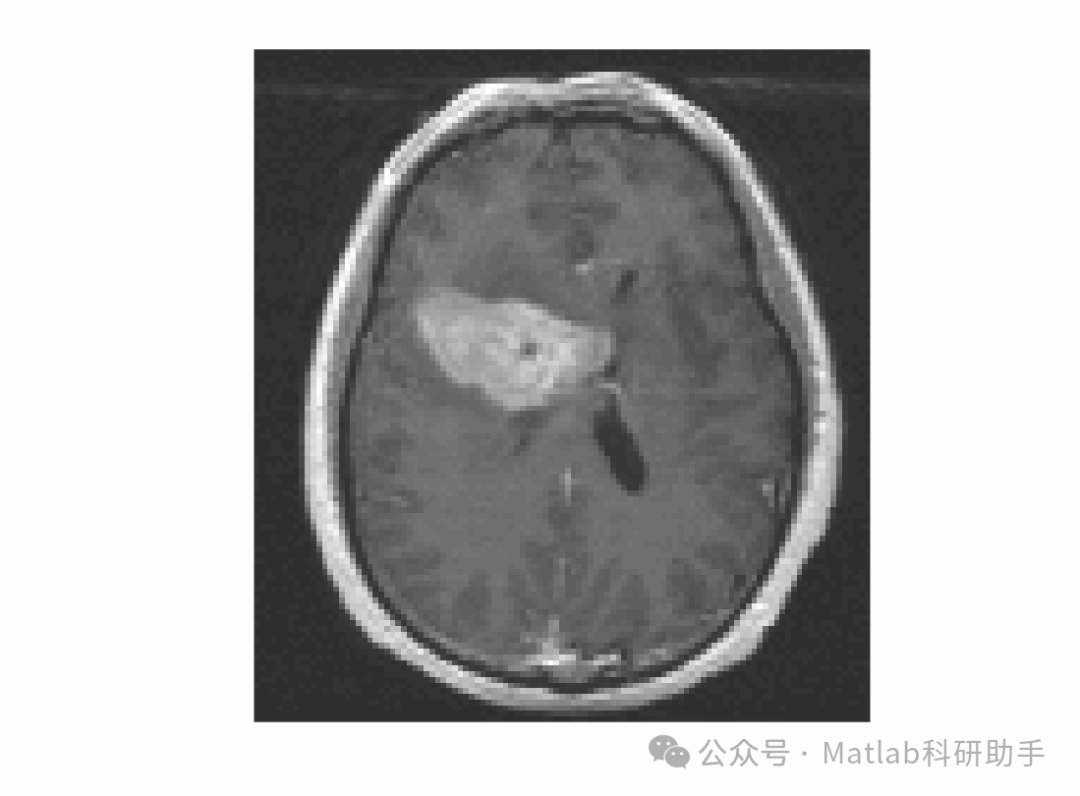

主动轮廓模型(Active Contour Model,ACM)作为一种自适应分割方法,通过构建能量函数引导曲线逐步收敛到目标边界,有效克服了传统算法对噪声敏感、依赖人工干预的缺陷,在医学影像(如肿瘤分割、器官提取)、遥感图像(如地物分类)等领域展现出显著优势。主动轮廓模型主要分为基于边缘和基于区域两类:基于边缘的模型(如 Snake 模型)依赖图像梯度信息,对弱边界和灰度不均匀图像分割效果较差;基于区域的模型(如 CV 模型)利用区域灰度统计信息,对灰度不均匀图像的适应性有所提升,但多采用全局灰度分布假设,难以准确描述图像局部灰度变化,在处理复杂纹理或强噪声图像时易出现轮廓泄漏、分割不准确等问题。

针对上述不足,本研究提出一种由局部高斯分布拟合能量驱动的变分水平集活动轮廓模型。该模型通过引入局部高斯分布拟合(Local Gaussian Distribution Fitting,LGDF)能量,充分利用图像局部区域的灰度统计特性,更精准地刻画图像局部灰度不均匀性;同时采用变分水平集方法表示活动轮廓,避免传统参数化模型拓扑结构固定的局限,实现对复杂形状目标的灵活分割。此研究不仅能够提升复杂图像的分割精度与鲁棒性,还能为医学诊断、工业质检等实际应用提供更可靠的技术支撑,具有重要的理论创新价值与实际应用前景。